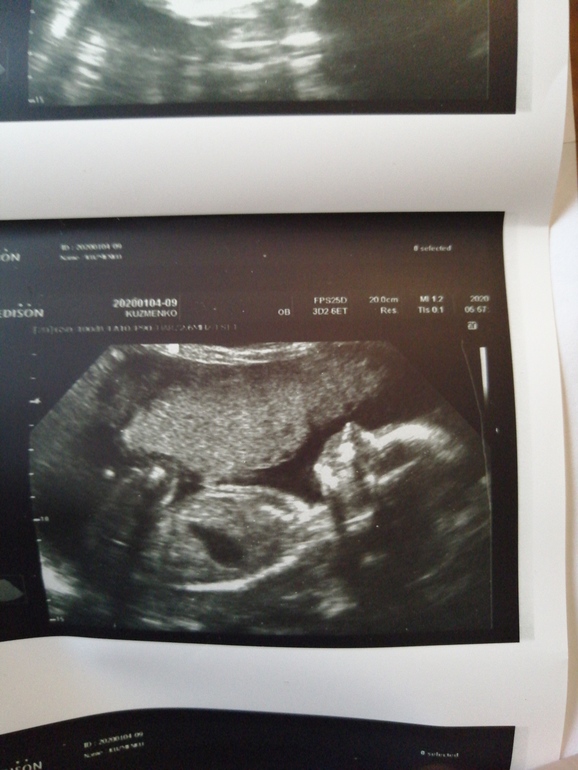

Мой внеплановый поход на узи (фото)

УЗИ, КТГ, доплерВрачи говорила контролировать тяж и ходить переодически на узи , сегодня как раз и решила сходить))) Аришка заметно подросла, догнали по срокам, ранее опаздывала на недельку почти, весит мой пузяш маленький уже 470 грамм, а самое радостное и важное ПРОПАЛ ЭТОТ АМНИОТИЧЕСКИЙ ТЯЖ🤗🤗🤗🎉🎉🎉🎉🥳🥳🥳🌼 Я довольна и спокойна😍🥰😊Ну и фоточки моей бубочки, 22 недели и 3 дня